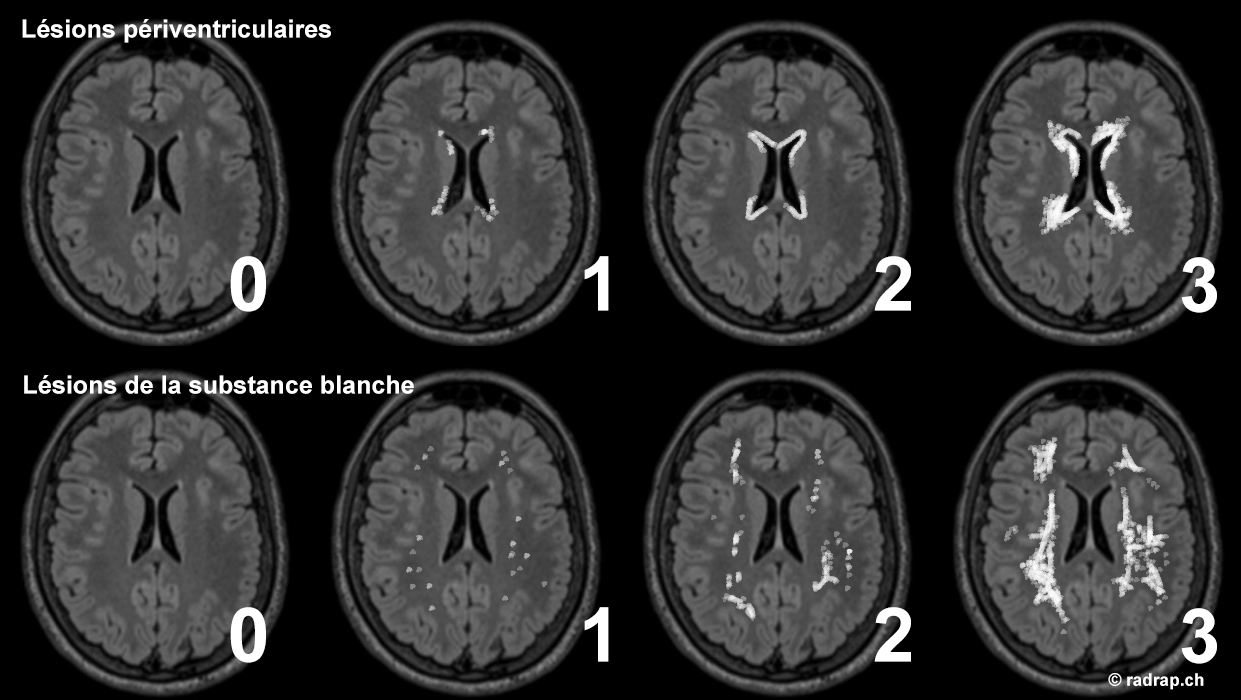

Classification Fazekas

Lésions périventriculaires :

0 = Pas de lésion

1 = Punctiformes ou fines lignes

2 = Halo

3 = Extensives à la substance blanche

Lésions de la substance blanche profonde :

1 = Punctiformes

2 = Confluence débutante

3 = Multiples zones confluentes